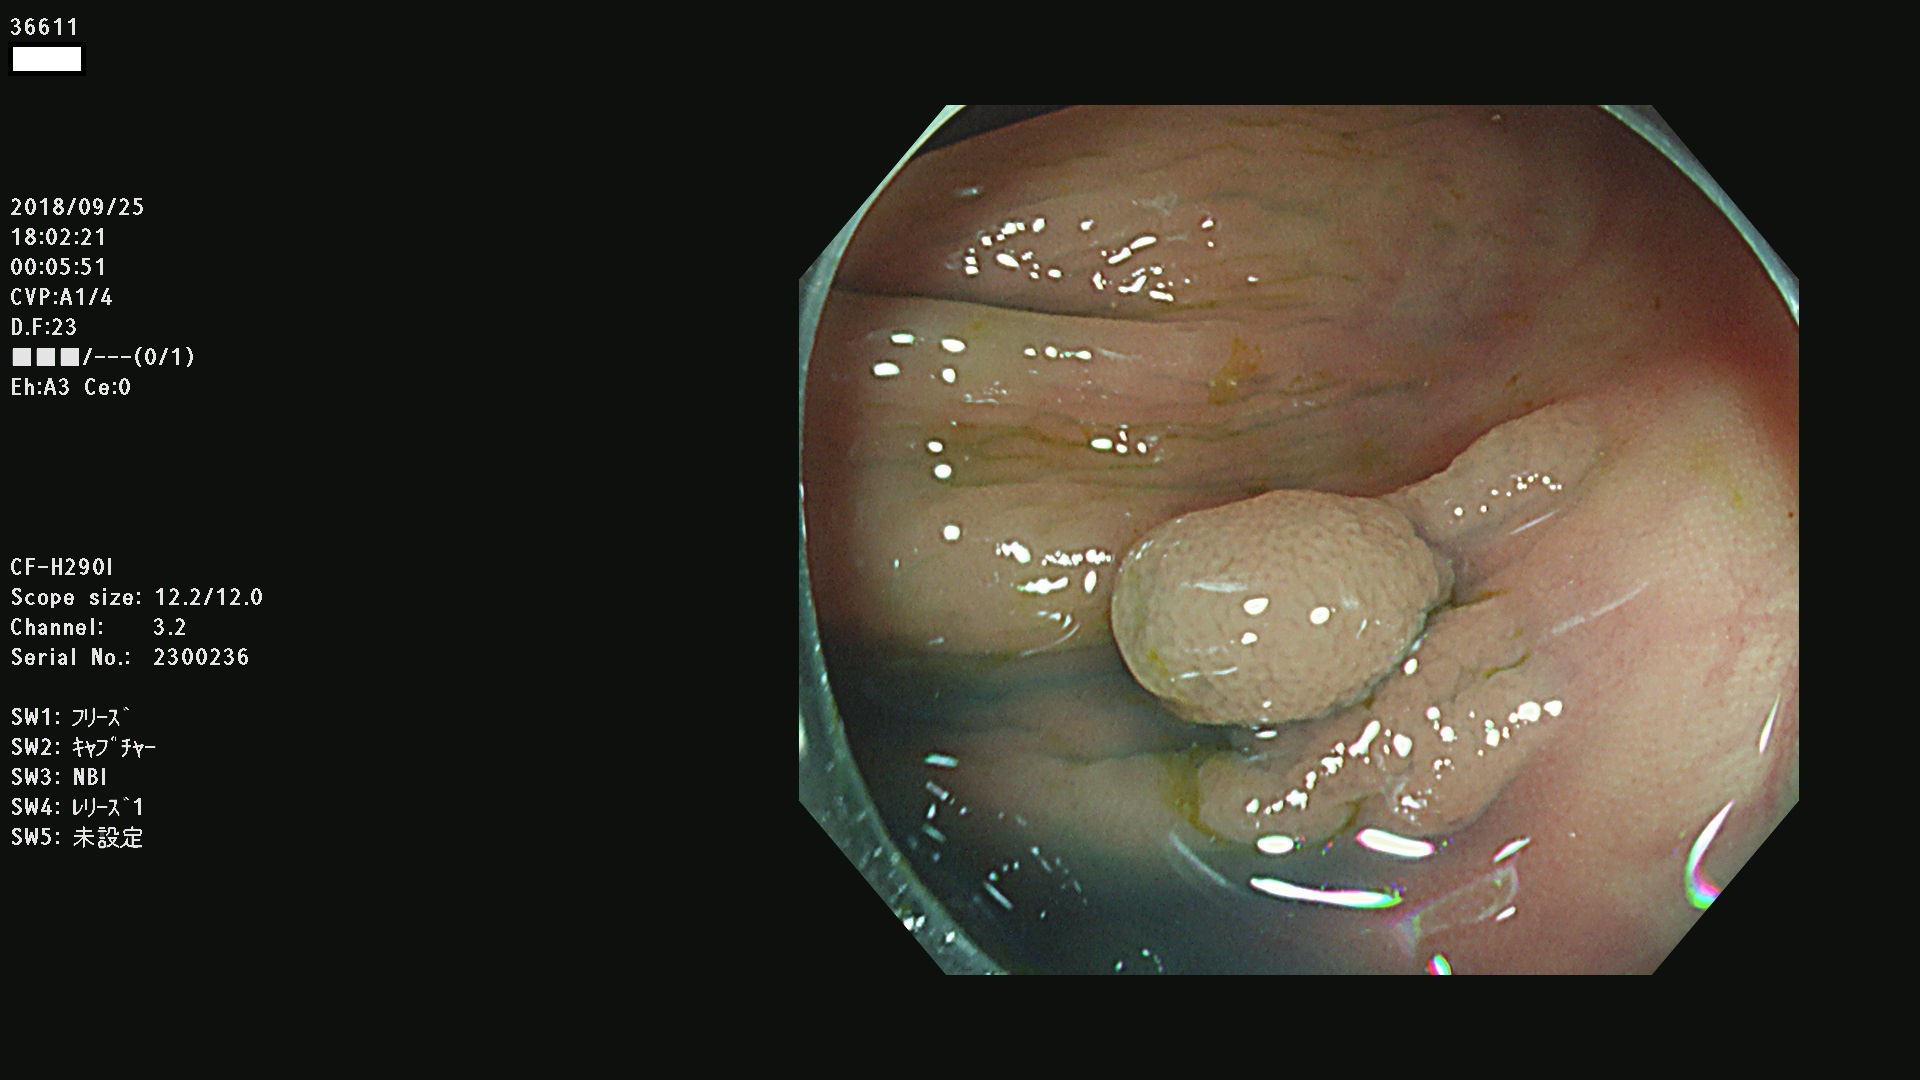

36600 36601 36603 36605 36606 36608 36609 36610 36611 36612 36613 36615 36617 36620 36621 36624 36625 36626 36627 36628 36629 36631(SSAPのみ) 36632 36633 36634 36636(SSAPのみ) 36637(SSAPのみ) 36639 36640 36642 36643 36644 36646 36647 36648 36649(SSAPのみ) 36650(SSAPのみ) 36652 36653 36654 36655(SSAPのみ) 36656 36657 36658 36659 36660 36661(SSAPのみ) 36665 36668 36669 36672 36673 36676 36677 36678 36679 36681 36682 36683 36684 36685 36687(SSAPのみ) 36691 36692 36693 36694 36695 36696 36697 36699(SSAPのみ)

発見困難で危険性の高い平坦型病変(上記100名より抽出)